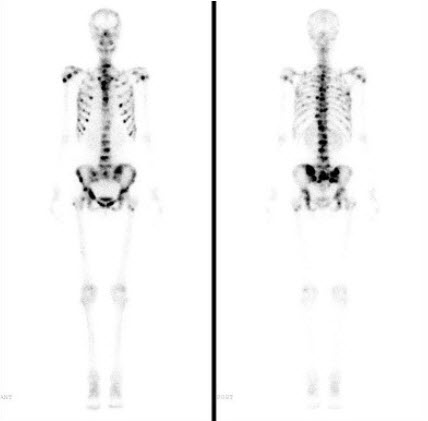

女性,78岁,头颅胀痛3个月,肾功能明显受损,HGB56g/L,行全身骨显像,最可能的诊断是()

A.肾性骨营养不良

B.原发性骨质疏松

C.骨软化症

D.Paget病

E.骨转移瘤